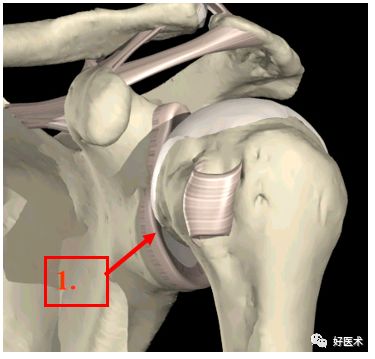

盂唇和盂肱韧带

1.盂唇

2. 盂肱上韧带

3. 盂肱中韧带

4.盂肱下韧带

5. 关节盂

6.腋下袋

肩峰下囊:肩峰下囊是个潜在的空间